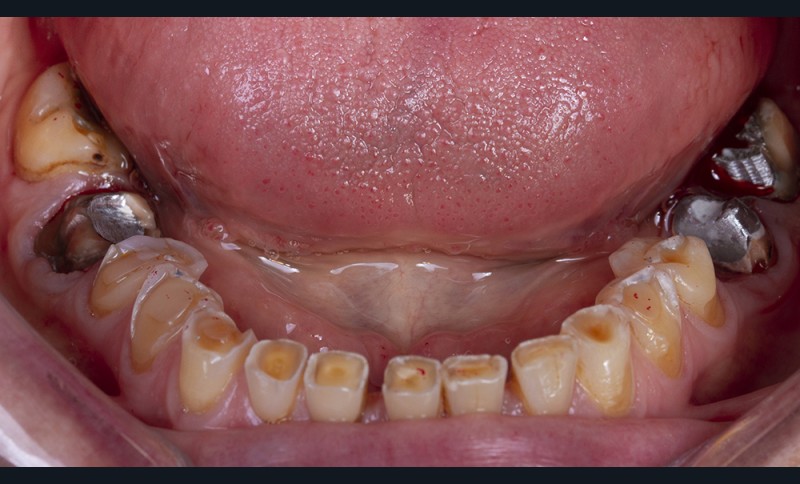

Dans un deuxième temps, un wax-up global permet de restaurer les courbes d’occlusion. Il est à noter que la présence d’égressions dentaires, faute d’antagoniste ou d’anciennes restaurations prothétiques inadaptées, crée des usures inégales au sein de la cavité buccale. Aussi, la présence de zones non recouvertes par le wax-up dans les secteurs postérieurs est courante, permettant ainsi la préservation de zones amélaires majeures pour le collage (fig. 2).